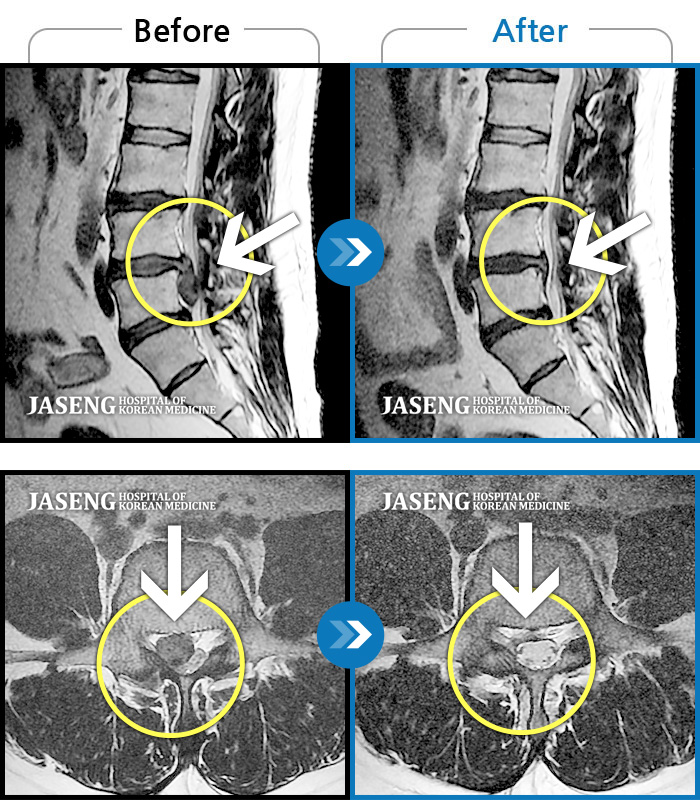

25년 1월 허리통증이 시작되고 잠을 잘수도없고 걸을 수 없을만큼의 상태가 되었을때 다시 김태용 원장님께 진료를 받고 예전 허리수술의(4번5번)(3번4번)디스크탈출증 재발과 협착증의 진단을 받고 지금까지 기나긴 여정의 입원 치료를 하며 곧 퇴원을 앞두고 있습니다.